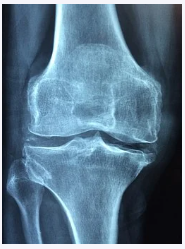

보스웰리아 효능에 있어서 가장 주된 효과는 관절 건강입니다. 다른 것보다도 관절에 굉장히 좋습니다. 이 안에는 ‘보스웰릭산’이라는 항염작용을 하는 성분이 들어있는데요. 이 ‘보스웰릭산’이 관절염을 개선시켜주어 관절 건강에 좋은 것이죠. 그래서 특히 관절염으로 고생하시는 분들이 자주 섭취하곤 합니다.

연골은 재생이 불가능하기 때문에 관리를 잘 해줘야 하는데요. 연골은 70%가 소모 돼도 인지를 잘 못한다고 합니다. 만약 통증이 느껴지면 그때는 이미 70%이상 진행이 된 것이죠. 그러므로 미리미리 관리를 해줄 필요성이 있습니다.